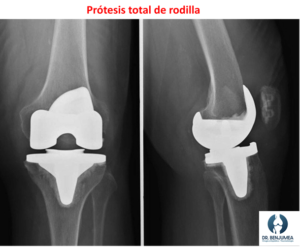

Prótesis de rodilla

La prótesis de rodilla (artroplastia de rodilla) es el tratamiento definitivo de la artrosis de rodilla. El traumatólogo la recomienda cuando el dolor y la perdida de función de la pierna para realizar actividades normales no se logran con el tratamiento conservador y las infiltraciones. Consiste en realizar unos cortes en el hueso enfermo y colocar implantes metálicos que sustituyen a la articulación desgastada.

Las prótesis pueden ser completas (Prótesis total de rodilla) o sustituir la mitad enferma de la rodilla (Prótesis unicompartimental de rodilla). Ocasionalmente en personas que padecen lesiones complejas en los ligamentos, habrá que colocar prótesis especiales que nos ayudan a sustituir su función para tener una prótesis estable. Aunque la prótesis de rodilla es una cirugía compleja, los resultados suelen ser muy buenos y los pacientes intervenidos logran eliminar el dolor, recuperar la movilidad y volver a realizar sus actividades de forma normal.